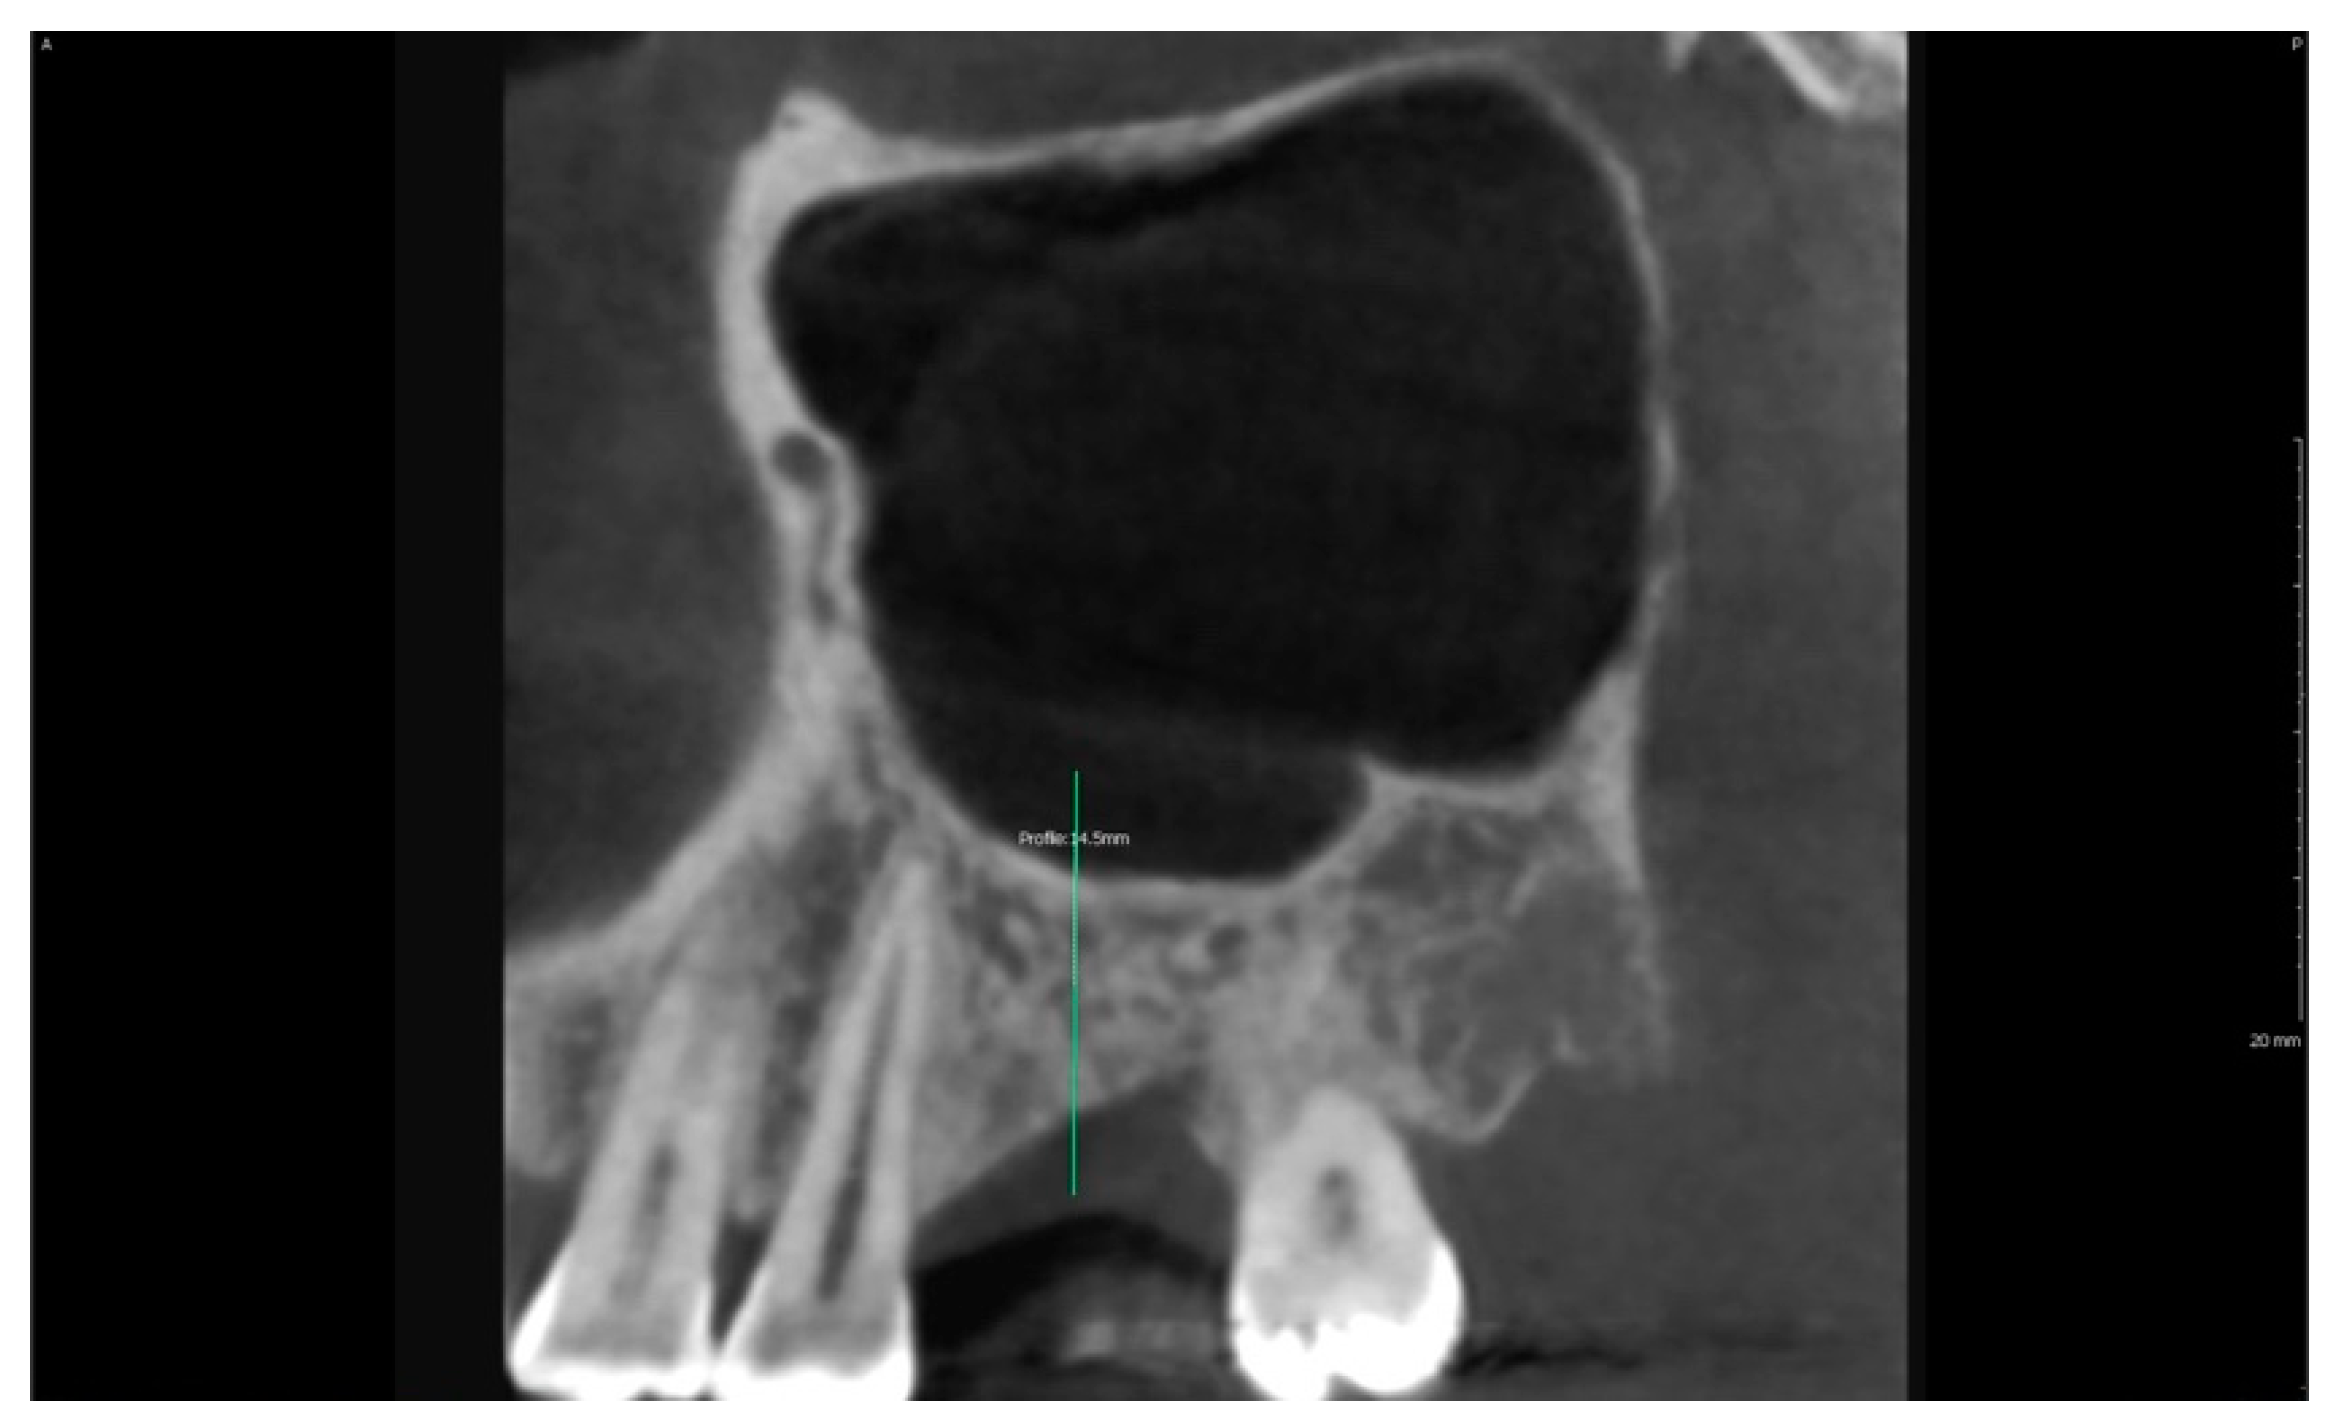

| 8 | f | 39 | 1 | 16 | 4.5 mm | 4.2 × 10 mm | 11 mm | 6.5 mm |